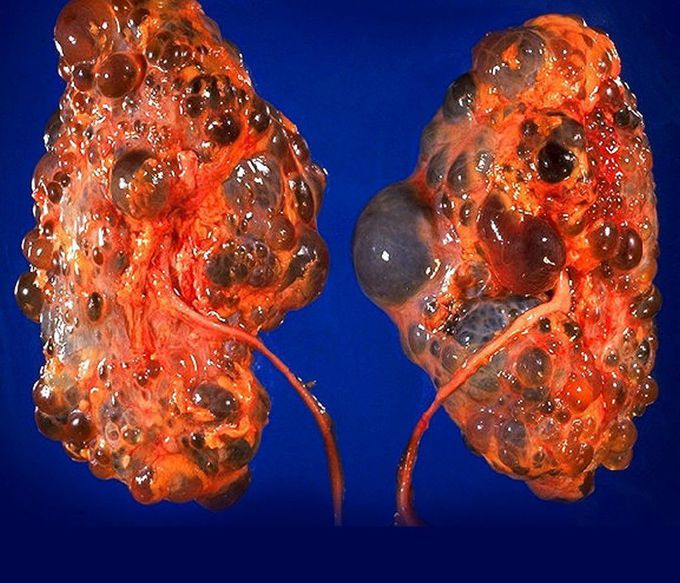

Autosomal Dominant Polycystic Kidney Disease

As the name indicates, it's an autosomal dominant disease that involves formation of clusters of cysts within the kidneys. It usually occurs in adults aged between 30 to 40 years but it can also occur in children. The cysts gradually increase in size and damage the surrounding renal tissue. It is due to genetic mutations out of which PKD1 mutation is known to account for most of the cases. The clinical features include bilateral, palpable kidneys, hematuria, pain in the abdomen or back, feeling of fullness in the abdomen. It can lead to hypertension, UTIs, berry aneurysms and even hepatic cysts! The cyst growth can be slowed by giving Tolvaptan. ADPKD patients need to have their blood pressure kept under control. Moreover, any developing complications need to be treated accordingly. However, patients who develop ESRD (end-stage renal disease) only benefit from renal replacement therapy.